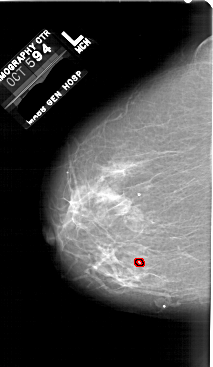

A_1760_1.RIGHT_CC

RIGHT_CC LINES 5641 PIXELS_PER_LINE 3571 BITS_PER_PIXEL 12 RESOLUTION 43.5 NON_OVERLAY

FILE: A_1760_1.LEFT_CC.OVERLAY

TOTAL_ABNORMALITIES 1

ABNORMALITY 1

LESION_TYPE CALCIFICATION TYPE PLEOMORPHIC DISTRIBUTION CLUSTERED

ASSESSMENT 4

SUBTLETY 2

PATHOLOGY BENIGN

TOTAL_OUTLINES 1

BOUNDARY